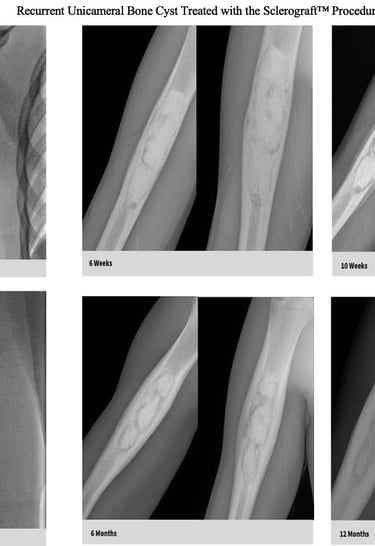

Quick recovery and bone formation seen between 6 weeks to 3 months

Follow-up imaging is usually obtained at 6 weeks, 3 months, 6 months, 12 months and annually for at least 3 years.

The long term follow-up with x-rays is critical because of the possibility of bone cyst recurrence. Generally, if a recurrence occurs, it tends to be noticeable by the 6 month mark

Gallery

Explore our educational resources and images